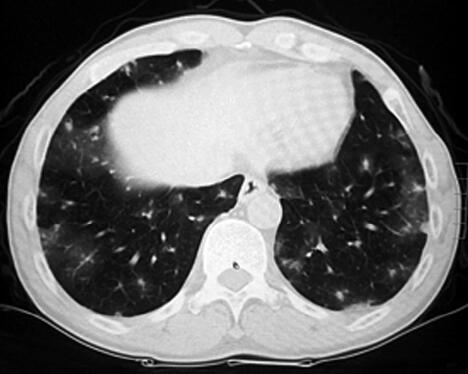

患者为农民,主要从事家务。既往身体健康,无呼吸系统疾病。半年前开始出现少量痰中带血,无明确诱因,其后咯整口鲜血,无胸痛,有轻度活动后气短。于当地诊所检查,胸部CT示双肺多发磨玻璃影,团片影、边缘呈晕轮征(图1)。给予抗感染及止血对症治疗(具体不详),咯血有所减轻。两个月前,患者为明确诊断就诊于我院,进行免疫生化检测时发现P-ANCA(±),诊断为弥漫性肺泡出血,肺血管炎可能性大,止血治疗的同时给予甲泼尼龙治疗,咯血症状消失,气短有所缓解,复查胸部CT:晕轮征及磨玻璃影有所吸收(图2)。继续甲泼尼龙24mg,每日1次,院外口服治疗。患者应用甲泼尼龙1个月后减量至每日20mg,但此后应用不规范,剂量波动于每日16~20mg。患者于入院前半个月再次出现痰中带血,伴胸闷气短,咯血量有增加趋势。

图1

本例患者病初磨玻璃影和晕轮征,结合咯血病史,考虑可能的诊断为血管炎是正确的。同时需要注意晕轮征缺乏特异性,但对缩小鉴别诊断范围有一定的帮助。另外,影像学需要动态评估,第一次就诊,在激素治疗后晕轮征有所吸收,而结节影没有吸收,应引起足够的重视去鉴别恶性疾病,引起晕轮征的常见恶性疾病包括:细支气管肺泡癌,肺鳞癌,肺腺癌,血管肉瘤,骨肉瘤,Kaposi肉瘤等。在诊断不确切时,如果病情允许,应积极进行组织病理学检查。